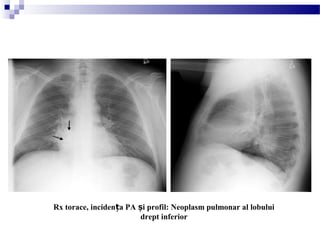

Rx torace, inciden a PA i profil: Neoplasm pulmonar al lobuluiț ș

drept inferior